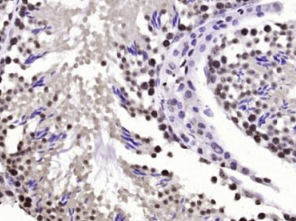

多聚甲醛固定,石蜡包埋(小鼠睾丸);经柠檬酸钠缓冲液(pH6.0)煮沸15min后获得抗原;用3%过氧化氢阻断内源性过氧化物酶20分钟;阻断缓冲液(正常山羊血清)37℃30min;用(BPTF)多克隆抗体进行抗体孵育在4°C下1:200整晚未结合的全身,然后根据SP试剂盒(兔子)说明和DAB染色进行操作。